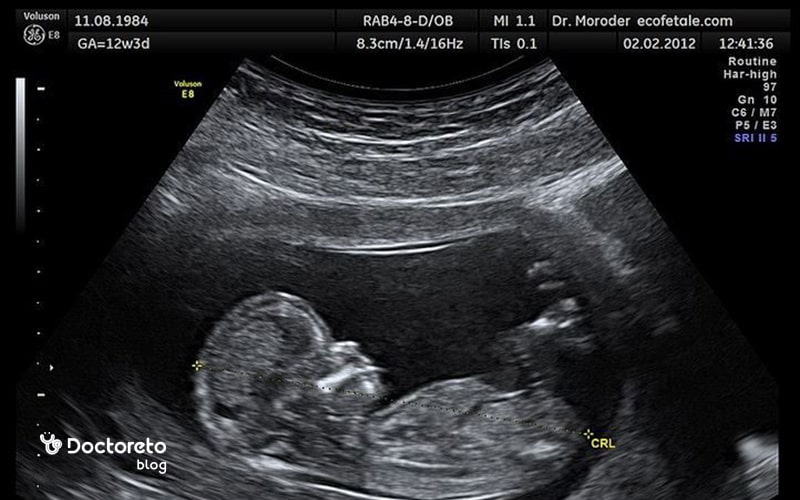

اکوژن در سونوگرافی بارداری

اکوژن در سونوگرافی بارداری به نواحی گفته میشود که امواج صوتی را بیشتر بازتاب میدهند و در تصویر روشنتر دیده میشوند. این نواحی میتوانند در جنین یا جفت دیده شوند و معمولاً نشاندهنده بافتهای متراکمتر یا ساختارهای خاص هستند. ممکن است پزشک در سونوگرافی بارداری متوجه نواحی اکوژن غیرطبیعی در بدن جنین شود که به شرح زیر هستند:

- توده اکوژن قلبی که شامل تجمع رسوب کلسیم در عضله قلب جنین است. این اکوژن در اکثر موارد بیخطر است و هیچ تاثیری بر سلامت جنین ندارد. اما در موارد نادر، این وضعیت ممکن است با برخی ناهنجاریهای کروموزومی مرتبط باشد. در چنین شرایطی، پزشک ممکن است برای اطمینان بیشتر، آمنیوسنتز (نمونهگیری از مایع آمنیوتیک) را توصیه کند تا بررسیهای ژنتیکی انجام شوند.

- اکوژن غیرطبیعی در روده جنین نیز نوع دیگری از اکوژن است که میتواند علل مختلفی داشته باشد. یکی از دلایل این وضعیت خونریزی داخل آمنیوتیک و بلع خون توسط جنین است که وضعیتی بیخطر و موقت در نظر گرفته میشود. گاهی نیز این اکوژن دلایل جدیتری نظیر عفونت داخل رحم (مثل توکسوپلاسموز یا سیتومگالوویروس) یا انسداد روده جنین دارد.